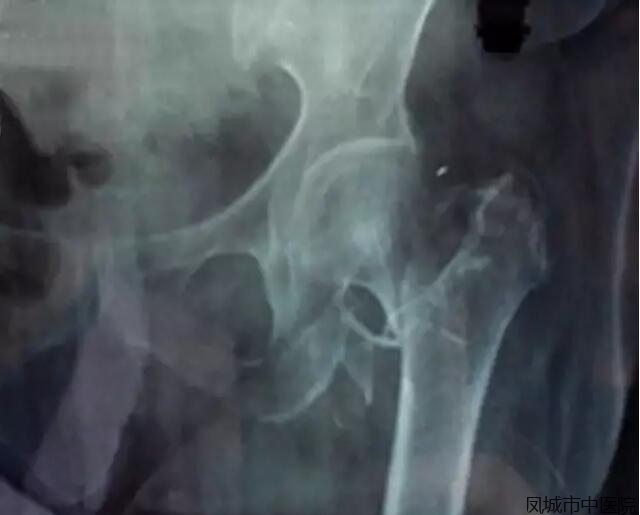

该患者,女性,86岁,干活时不慎摔倒,致左股骨粗隆间粉碎性骨折并股骨颈骨折来院。

老年股骨粗隆间骨折是比较难处理的骨折,不手术、卧床时间长、死亡率高,行关节置换,能让老人尽快离床活动,减少并发症的发生。但该患者年龄较大,心肺功能较差,并合并其他内科疾病,手术、麻醉风险较大.